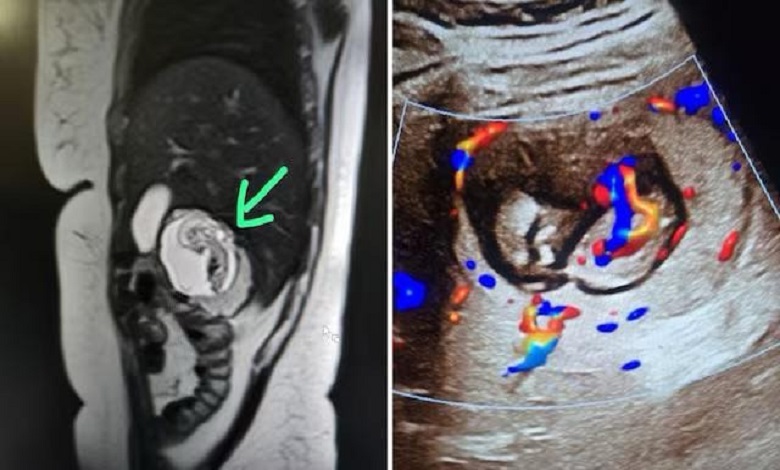

India’s first intrahepatic ectopic gestation with a 12‑week foetus growing in the liver, posing extreme medical risk.

Truth Of Bengal: উত্তরপ্রদেশের মীরাটে এক ৩০ বছর বয়সী মহিলার গর্ভাবস্থা নিয়ে চাঞ্চল্য ছড়িয়েছে(Liver Pregnancy)। চিকিৎসকরা জানিয়েছেন, তাঁর সন্তান জরায়ুতে নয়, বরং লিভারের ডান প্রকোষ্ঠের প্যারেনকাইমাল টিস্যুর গভীরে বেড়ে উঠছে। ঘটনাটি চিকিৎসকদের বিস্মিত করেছে, কারণ এটি চিকিৎসা বিজ্ঞানে অত্যন্ত বিরল ঘটনা, যাকে ‘ইন্ট্রাহেপ্যাটিক এক্টোপিক প্রেগন্যান্সি’ বলা হয়। বিশ্বে এ পর্যন্ত মাত্র আটটি এমন কেস পাওয়া গেছে। এটি সম্ভবত ভারতে এই ধরনের প্রথম ঘটনা।

কয়েক সপ্তাহ ধরে পেটে অসহ্য ব্যথা এবং বমি বমি ভাব নিয়ে ওই মহিলা চিকিৎসকের কাছে যান(Liver Pregnancy)। প্রাথমিক ইউএসজি রিপোর্টে রোগ নির্ণয় করা সম্ভব না হওয়ায়, চিকিৎসকরা এমআরআই করার পরামর্শ দেন। এমআরআই রিপোর্টে দেখা যায়, তিনি গর্ভবতী, কিন্তু ভ্রূণটি লিভারে অবস্থান করছে এবং তার জরায়ু সম্পূর্ণ খালি। চিকিৎসকরা জানিয়েছেন, ভ্রূণের হৃদস্পন্দন স্বাভাবিক রয়েছে।

চিকিৎসকরা এই ধরনের গর্ভাবস্থাকে অত্যন্ত বিপজ্জনক বলে মনে করছেন। লিভারে প্রচুর রক্তনালী থাকায় ভ্রূণ বড় হওয়ার সাথে সাথে রক্তনালীর উপর চাপ সৃষ্টি হতে পারে, যা লিভার ফেটে যাওয়ার কারণ হতে পারে(Liver Pregnancy)। অস্ত্রোপচারের মাধ্যমে ভ্রূণ অপসারণ করা যেতে পারে, তবে এটি অত্যন্ত ঝুঁকিপূর্ণ প্রক্রিয়া।